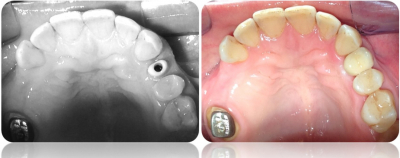

Gallery